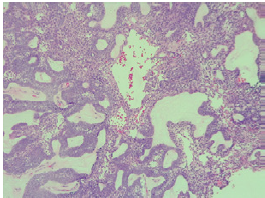

A contrasted CT scan of the neck and paranasal sinuses was performed, identifying a mass involving the left mandibular region and the pterigopalatine fossa with associated bone destruction; a biopsy with histopathological study report was also performed, showing follicular and plexiform ameloblastoma. Taking into account the findings of the tomography and the reports from the pathologist, ameloblastoma was diagnosed without a doubt. Extension studies were also performed with chest CT and cervical lymph node puncture biopsy, ruling out distant disease. The case was discussed during a multidisciplinary meeting where a left partial mandibulectomy, mandibular condyle reconstruction with plaque and fibula free flap were established as management. The pathology of the surgical specimen showed tumor-free edges and surgical margins of 10mm (Figure 1).

Source: Document obtained during the study.

Figure 1 Histopathology of mandibulectomy with evidence of follicular ameloblastoma and odontogenic epithelial islands with peripheral columnar cells.